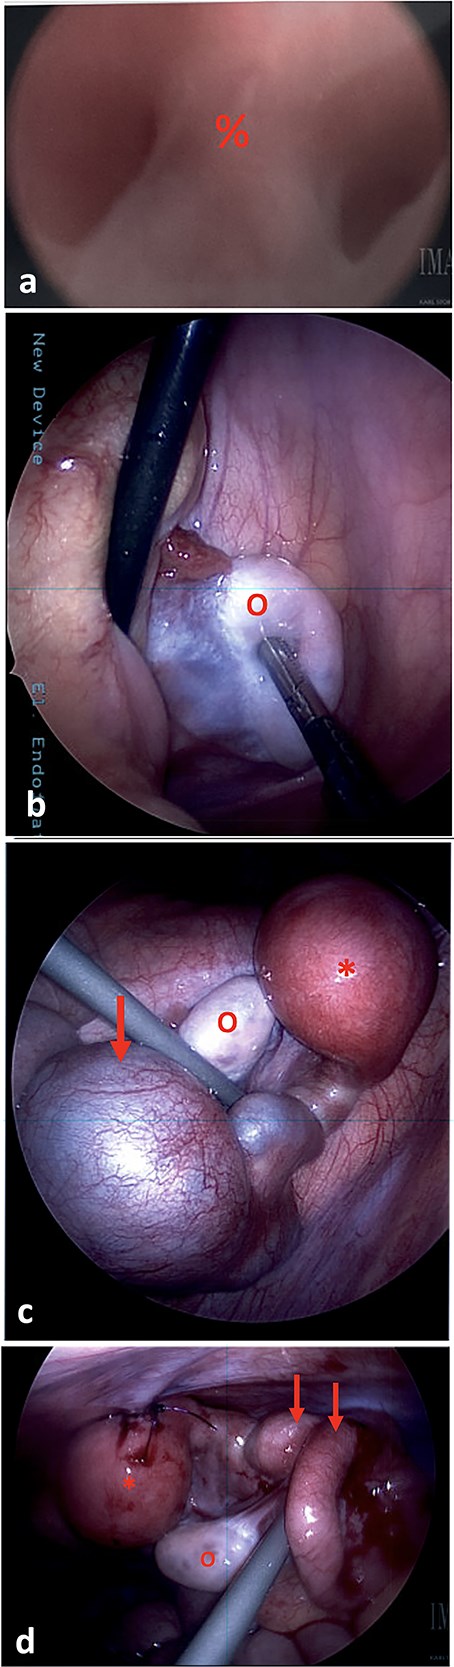

(a) On vaginoscopy, a central septum (%) was noted, suggestive of a longitudinal vaginal septum or hemi-vaginas. (b) Laparoscopic photograph showing the left ovary (o) located in the left lower pelvis, not attached to any tubal structure. (c) Laparoscopic photograph demonstrate a right-sided hypertrophic uterus (*), significantly dilated and firm due to retained blood, and a markedly dilated and tortuous right fallopian tube (arrow). The right ovary appeared normal (o). (d) The uterine dome (*) was sutured to the abdominal wall. The right fallopian tube was decompressed after aspiration (arrows).

The cystic segment of the fallopian tube was laparoscopically punctured and 60 ml of dark blood was aspirated. The uterine fundus was separately punctured and 40 ml of dark blood was aspirated, consistent with hematometra. A 10Fr silicone Foley catheter was inserted into the uterine dome using a hook cautery device. The balloon was inflated, and the uterus was affixed to the abdominal wall with 2-0 PDS sutures (Fig. 2d).